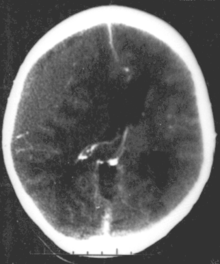

CT scan showing epidural hematoma, a type of traumatic brain injury (upper left)

Brain trauma in the developing human is a common cause (over 400,000 injuries per year in the US alone, without clear information as to how many produce developmental sequellae)[41] of neurodevelopmental syndromes. It may be subdivided into two major categories, congenital injury (including injury resulting from otherwise uncomplicated premature birth)[6] and injury occurring in infancy or childhood. Common causes of congenital injury are asphyxia (obstruction of the trachea), hypoxia (lack of oxygen to the brain), and the mechanical trauma of the birth process itself.[42]